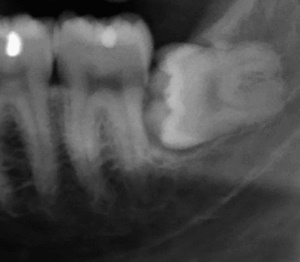

사랑니란?

우리가 사랑니라고 부르는 것은 큰 어금니 중 세 번째 위치에서 제일 마지막에 나오는 치아입니다. 사랑니가 나올 때에는 첫사랑을 하듯이 아프다고 하여 붙여진 이름이라고 하는데요. 다른 이름으로는 ‘지치’라고 합니다. 지치는 사리를 분별할 수 있는 지혜가 생긴다는 뜻입니다.

사랑니는 보통 큰 어금니와 비슷하게 생겼습니다. 사랑니의 형태나 크기는 매우 다양하다고 하는데요. 보통의 어금니 보다 깊이 나기 때문에 빼기 어렵거나 절개를 통해 힘들게 빼야 하는 경우가 많습니다. 원래 사랑니는 음식물을 갈아 내기 위한 용도라고 하는데요. 이것은 치아의 퇴화 현상이라고 생각하시는 분들도 많이 계십니다.